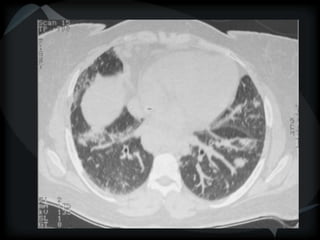

Emphysema - CL

Emphysema - PA

Hyperlucency

Centrilobular emphysema

Paraseptal emphysema

Panacinar emphysema